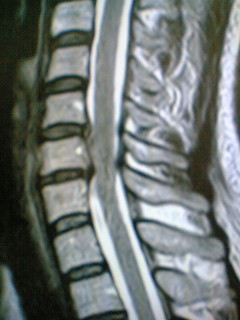

これは、首です。首を横から見ているところ。左が前ですね。

真ん中あたりに縦に走っているのが、神経で、その神経は、ここで白く見える、まぁ衣を着ているわけだけれども、その衣が、薄くなって、ひどい部分では、ハダカ・唐揚げですか、そんなような感じになっているわけですね。

先生いわく、ここらへんは夏服。冬なのに夏服! ここなんかもっとひどくて、裸の王様!。